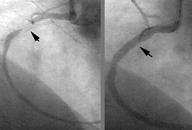

Damar açıcı cihaz ve yöntemler balon, stent (tel kafes), rotablatör (yüksek devirli matkap uçlu cihazlar), lazer ve diğer bazı yöntemler olarak sıralanabilir. Bunların hepsi tüm hastalarda kullanılabilir, ancak şeker hastalarının en büyük dezavantajı bu yöntemler kullanıldıktan sonra damarın ‘tekrar daralma' oranının yüksek olmasıdır. Günümüzde en çok kullanılan yöntem olan stentleri ele alacak olursak şeker hastalığı olmayan bir kişide ortalama %30 olan tekrar daralma oranı, şeker hastalarında %50-60 lara çıkmaktadır.

İlaç salınımlı stentler üzerlerine kaplanmış olan, damarın içe doğru kalınlaşmasını engelleyen bazı ilaçları yavaşça salgılarlar. İlacın salgılanma süresi stentin markasına, kullanılan ilaç ve ilacı taşıyan polimer denilen yapıların özelliğine göre değişmekle beraber 1-6 ay civarındadır. İlaç kaplı stentlerin sıkmasıyla beraber şeker hastalarında genişletilen koroner damarların tekrar daralma oranları %50 lerden %5-10 lara düşmüştür. Yapılan çalışmaların ön sonuçlarına göre, şeker hastalarında ilaç kaplı stent kullanılarak koroner damarlar açıldığında, koroner by pass cerrahisi ile aynı sonuçlar elde edilmekte, cerrahi operasyonun riski de hesaplandığında ilaç kaplı stent ile yapılan işlemler daha üstün gözükmektedir. Şeker hastalığı olmayan hastalarda da aynı üstünlükler söz konusudur ancak şeker hastaları kalp hastaları içindeki en yüksek riskli alt grubu oluşturduğundan elde edilen fayda da daha fazla olmaktadır. İlaç kaplı stent kullanılması için damarlardaki darlıkların stent yerleştirilmesine uygun olması gerekmektedir.